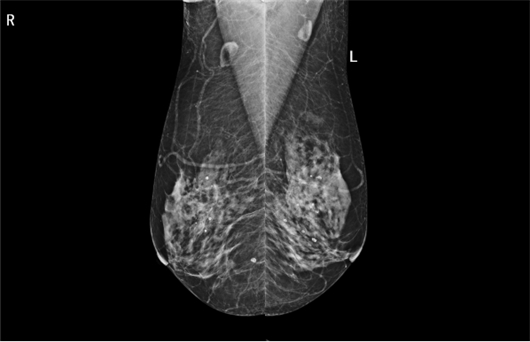

第二,CESM能谱成像,实现功能与解剖的完美融合。CESM技术通过静脉注射碘对比剂后,在单次压迫下完成低能与高能两次曝光,经减影处理后生成突出显示病灶血供的“减影图”,有效抑制致密腺体背景干扰。

(左侧为低能图,右侧为高能图)

CESM能谱成像临床价值显著,首先对于致密乳腺患者的诊断更精准,减影技术使隐藏于致密腺体中的强化病灶清晰显现,成为致密型乳腺患者的优选检查方式;其次,对于非肿块样病变的鉴别能力更强,对结构扭曲、不对称致密等病变,CESM的BI-RADS分类诊断准确率可达80.9%;再者,对于术前评估与分期更可靠,CESM在多灶病变检测准确率达96.5%,肿瘤大小测量与病理符合率63%(常规摄影仅34%),T分期准确率高达94%;最后,帮助新辅助化疗疗效评估,通过量化参数变化,可早期预测病理学完全缓解(pCR),为治疗方案调整提供依据。